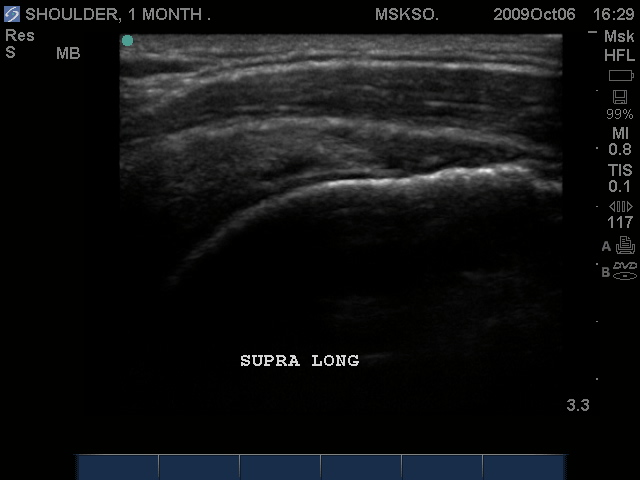

Long axis Supraspinatus tendon over lateral Greater Tuberosity. (lateral greater tuberosity is flat relative to the anterior) Tendon retraction is seen over cartilage interface sign of the humeral head.

Slightly anterior movement of the probe to visualize the full detail of the tear only for this case study purpose.